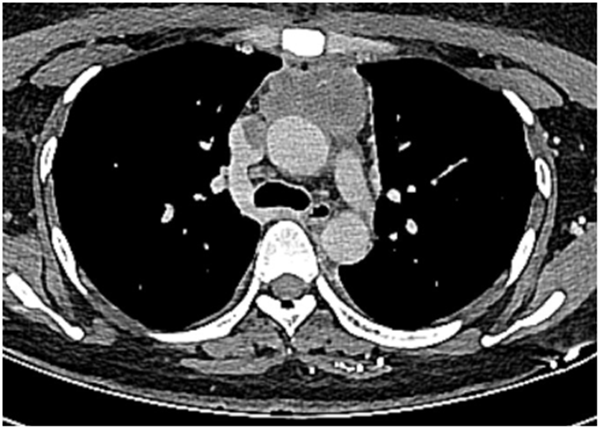

患者为一位35岁女性,一个月前出现出现颜面部肿胀,晨起明显,近1周来颜面部肿胀逐渐加重,为求手术治疗,来我院胸外科就诊并入院。胸部增强CT检查显示患者前上纵隔长有大小为5.0cm×3.0cm×2.5cm的肿瘤,紧邻双侧膈神经,已侵犯心包、上腔静脉及左侧无名静脉等胸腔大血管,且上腔静脉及左侧无名静脉内瘤栓形成,几乎完全阻塞管腔。患者初步诊断为前上纵隔肿瘤伴上腔静脉综合征,穿刺活检未能明确病理性质,患者家属手术愿望强烈。若要手术治疗,不仅需要仔细分离切除严重侵犯周围组织的肿瘤,还需阻断并切除受侵血管,不仅需要胸外科手术基础,更需要熟悉心脏、大血管解剖,灵活掌握复杂的血管吻合技术,选择合适的人工血管进行重建。此外,长时间阻断血管会使头部和上肢血液回流受阻,容易导致脑水肿和神经功能障碍,因此手术必须分秒必争,以最快的速度完成肿瘤切除与血管重建,尽量缩短上腔静脉阻断时间,同时还需确保血管吻合的可靠性与通畅性,对手术技艺的要求极高。人工血管重建后,体内容易形成血栓,围术期需加强抗凝治疗,但与此同时增加了术后出血的几率,对围术期出血与血栓的管理又提出更高的要求。手术难度极高,非常容易损伤胸腔内重要脏器、神经,造成非常严重的并发症甚至危及患者生命。